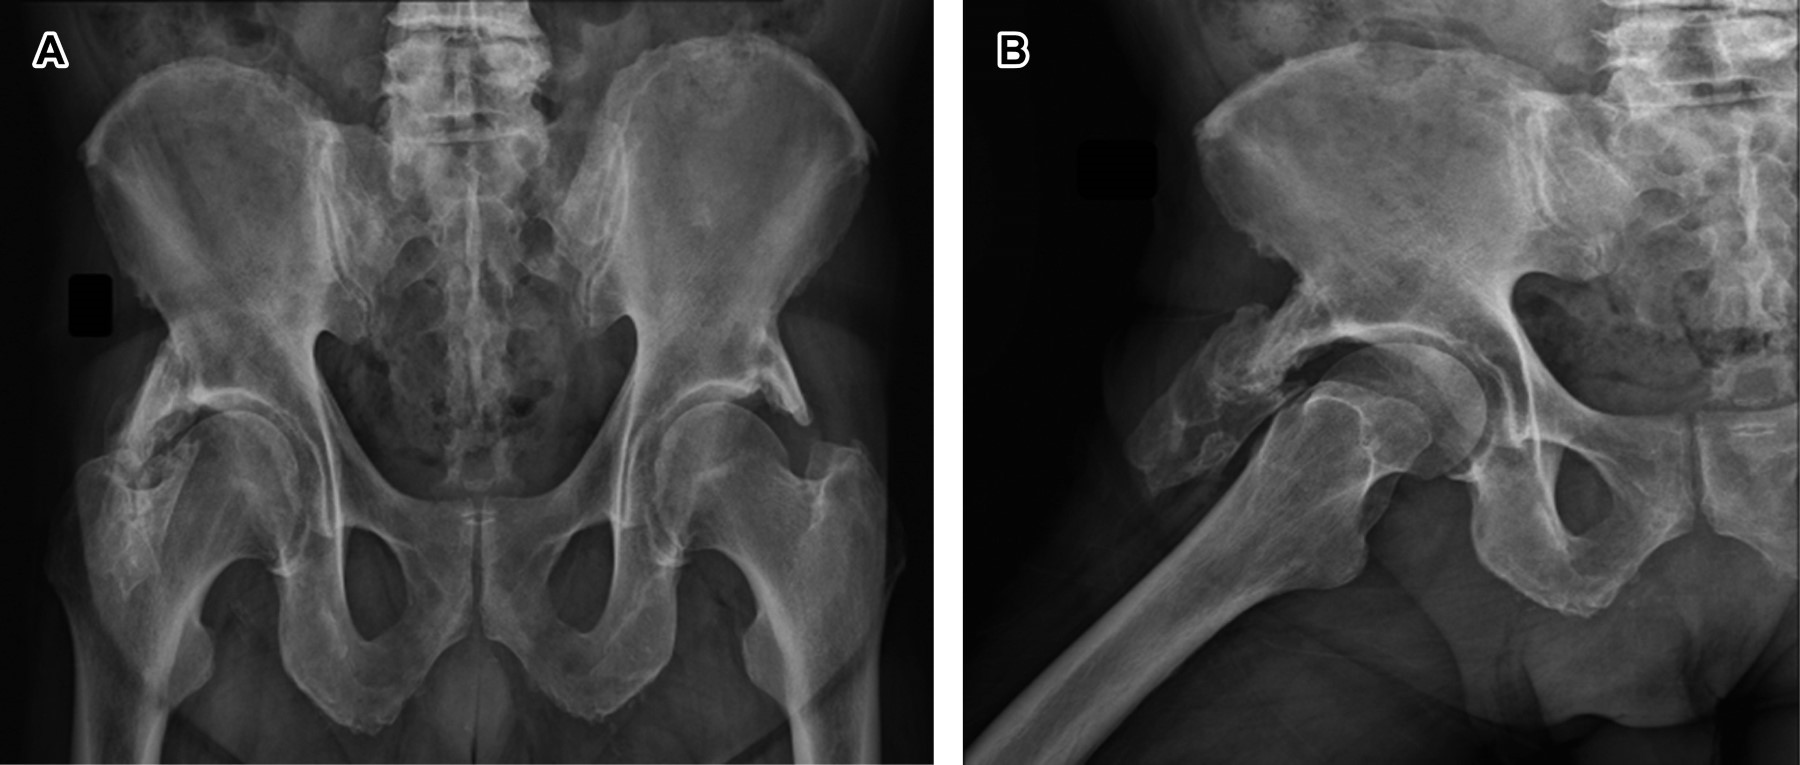

A 74-year-old male patient whose diagnostic impression was a discrete increase in synovial fluid in the right coxofemoral joint compared to the left side. The findings in the right hip suggested the possibility of bony prominences, considering the articulated right pelvic finger.

Figure 1